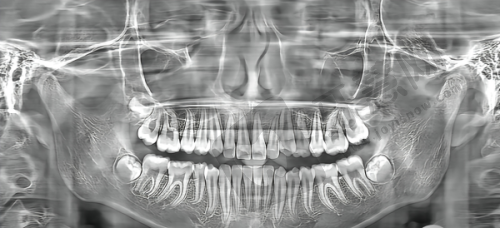

【医院简介】在种植牙领域有较高行业评价,医院环境优雅,设备精良,尤其在数字化口腔诊疗方面具备独特优势,能通过数字化扫描与设计提供个性化治疗方案。

【特色项目】以个性化种植牙方案为核心,结合患者口腔条件与需求定制,提升种植适配度与成效。

【特色项目】核心优势是微创种植技术与数字化全隐形矫正技术,前者减少种植创伤,后者通过数字化设计实现更精细的矫正成效。

【特色项目】专注微创种植牙、即刻负重种植与牙齿矫正,其中即刻负重种植能在种植后快速修复咀嚼功能,满足患者紧急需求。